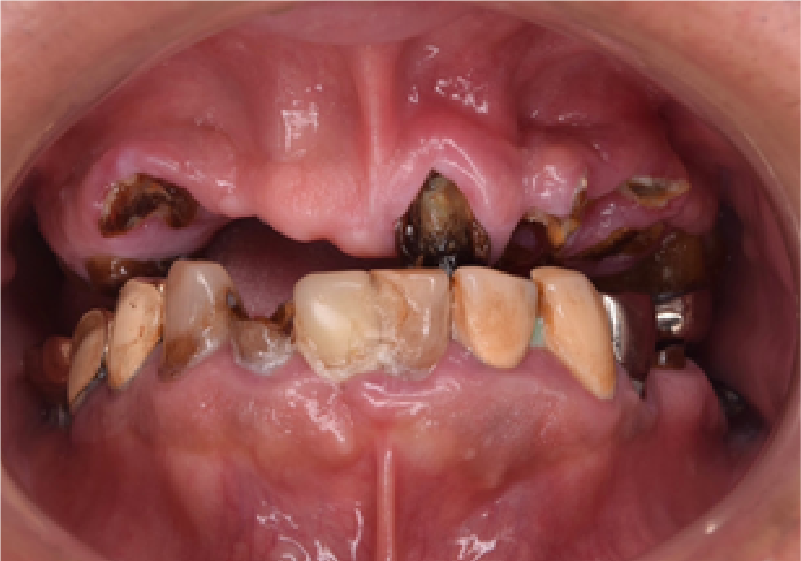

虫歯が多過ぎたり、抜けた歯があって、お口の中がボロボロなのに、本当にちゃんとキレイに治るんだろうか?という疑問をお持ちの方は多いと思います。

これにつきましては、完全にご安心下さい。

私たちは歯科治療のプロですので、さまざまな選択肢をご提案し、その中からあなたに合った方法を相談し、治します。

・糖尿病・早産/低体重出産・心筋梗塞・脳梗塞そして「患者さんの心」への問題です。歯が原因で「コミュニケーションが苦手」になっていませんか?ボロボロの歯でも、ちゃんとした歯科医院で治療することで、本当に綺麗に改善します。